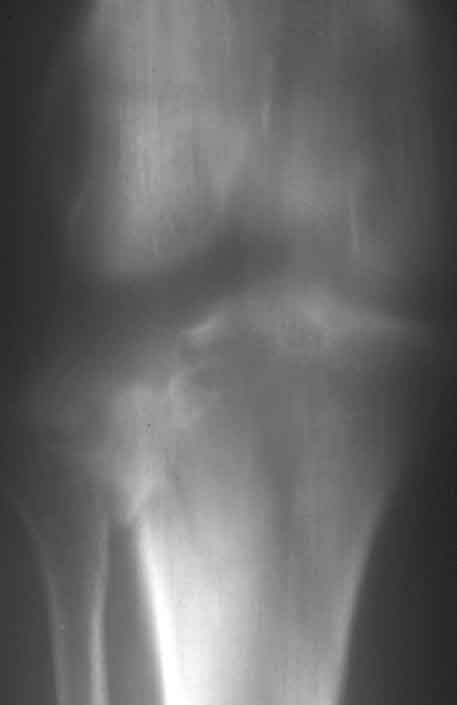

Laterale Impression des Tibiakopfes

Röntgenbefund nach einem Jahr

Gute Funktion nach einem Jahr. Patientin läuft schmerzfrei.